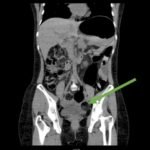

Computed tomography (CT) of the abdomen and pelvis was obtained revealing a colonic volvulus in the left mid to upper abdomen (blue arrow) involving the distal transverse colon and descending colon, with gaseous colonic distention to 8.5 cm (red arrow). The characteristic “whirl pattern” is also present (yellow arrow). These findings are suggestive of a high-grade colonic obstruction. It was without evidence of pneumoperitoneum, pneumatosis, or drainable collection. Of note, a 3.6 cm dermoid tumor is also observable in the left adnexa (green arrow).